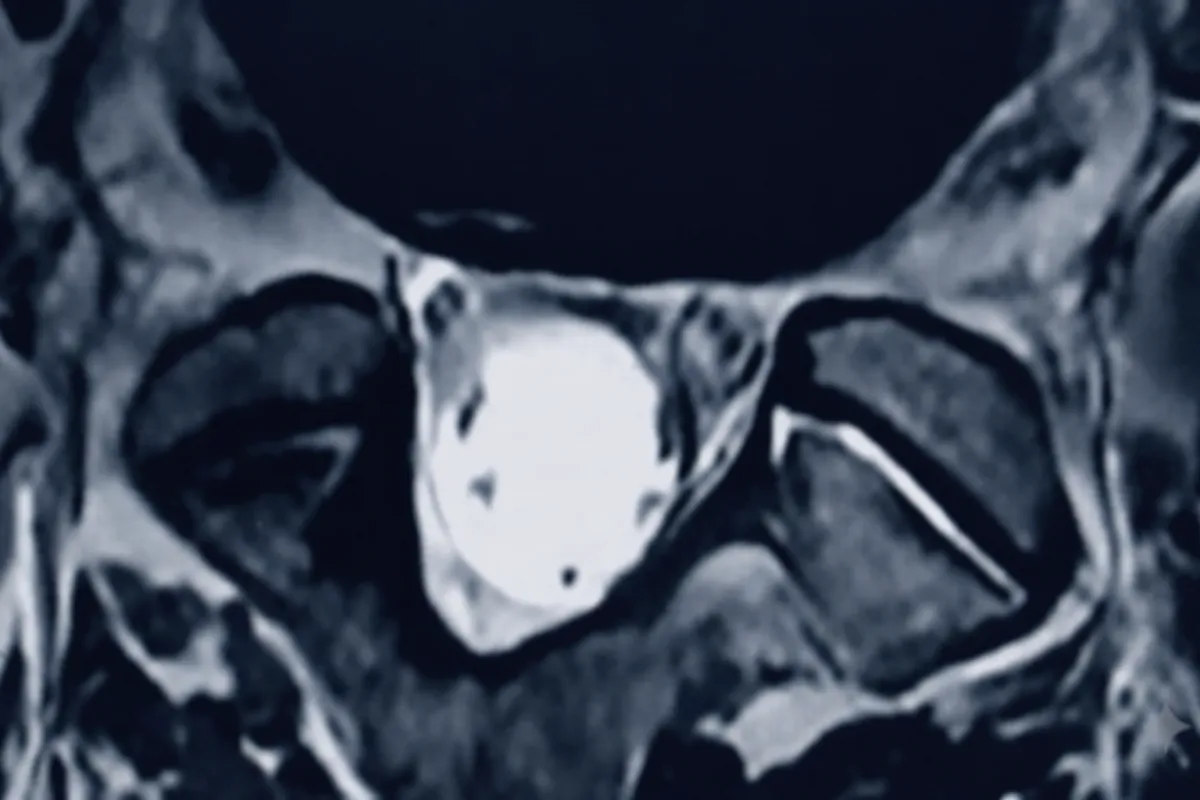

Spinal Instability & Symptomatic Disk, Joints and Ligaments

Platform identifies imaging findings related to spinal instability, symptomatic disc abnormalities, facet joint changes, and ligamentous injuries for physician review and clinical correlation.

Multi-Level Spine Analysis Example

Imaging shows findings consistent with instability at L4/5 and L5/S1 following prior percutaneous disc procedure. Board-certified physician review recommended for treatment planning.